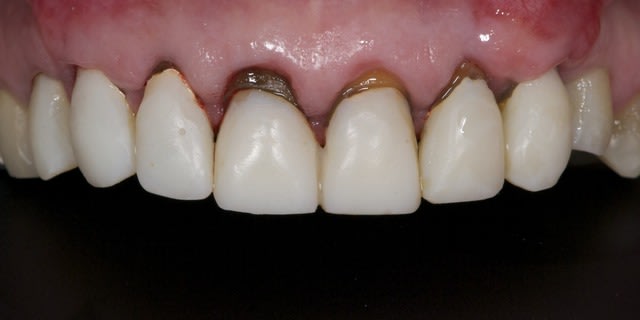

Aujourd'hui a 4 semaines:

A suivre reTR + moignon compo + tenon fibré + nouvelles prov dans les prochaines semaines.

La suite avec les deuxièmes provisoires en places, le projet esthétique étant validé, les emp. ont été réalisées, ceramo-metal sur moignon composite a venir..